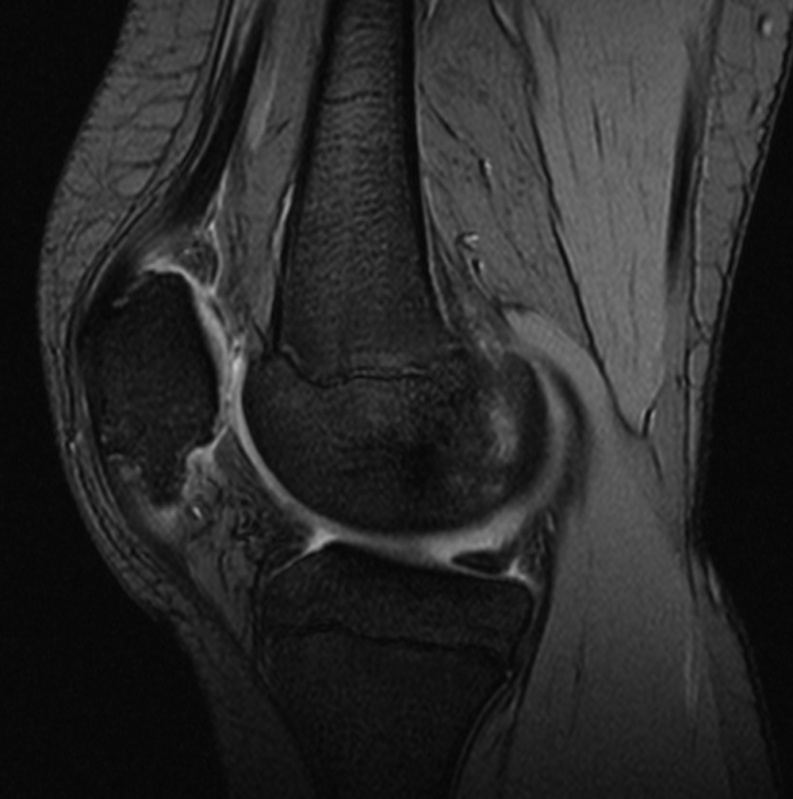

• Ressonância de joelho;